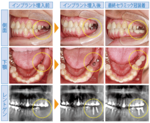

No.81 当院のインプラント治療について

2017/01/09

インプラント(人工歯根)とは、歯が抜けてしまったところの骨にフィクスチャー(ネジ)を埋め込んで、そのネジを土台にして人工の歯を装着する治療法です。

インプラントは見た目も自然で、骨内に固定されている...